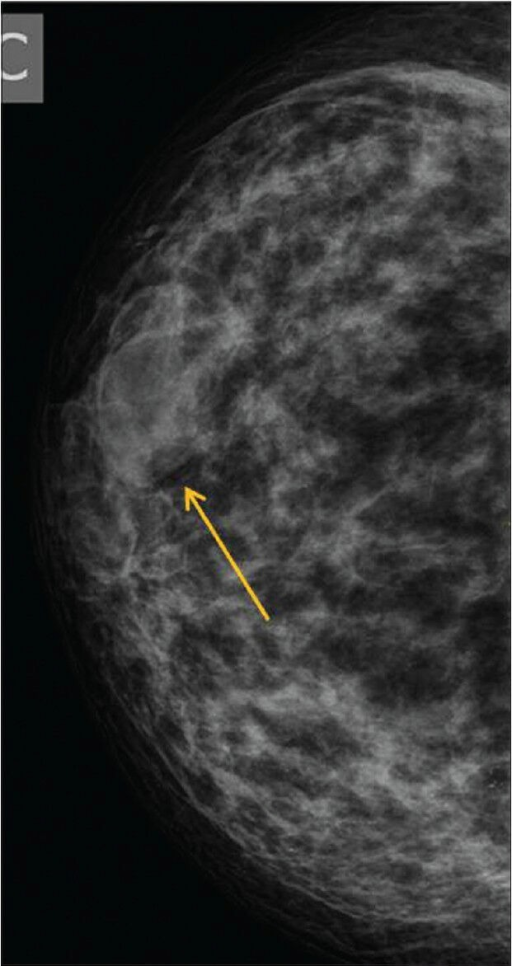

Fat Necrosis

Fat necrosis is caused by damage to fat cells, typically from direct trauma (e.g. seatbelt injury, biopsy, breast surgery such as implant removal or reconstruction). Radiation therapy and anti-coagulants may also cause fat necrosis to develop. Fat necrosis may be felt as a lump, otherwise it is detected via mammogram or ultrasound. They can resemble breast cancer on mammogram, so a biopsy may be needed to exclude malignancy. Usually fat necrosis will resolve on its own without treatment.